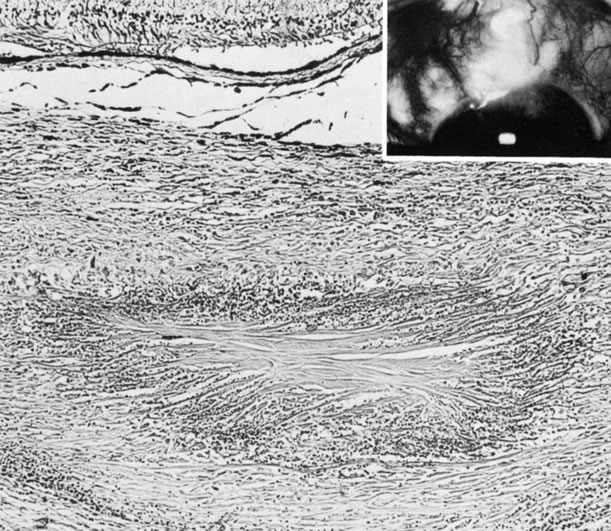

1992.

1982.